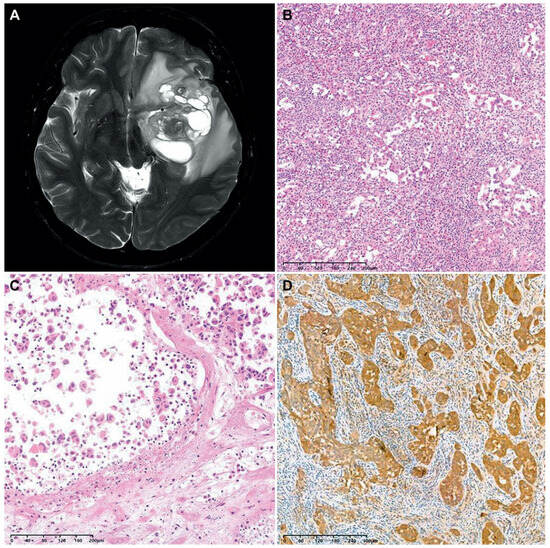

3.5. Brief Presentation of a Case of F3T3-Positive GBM Showing Unusual Histology